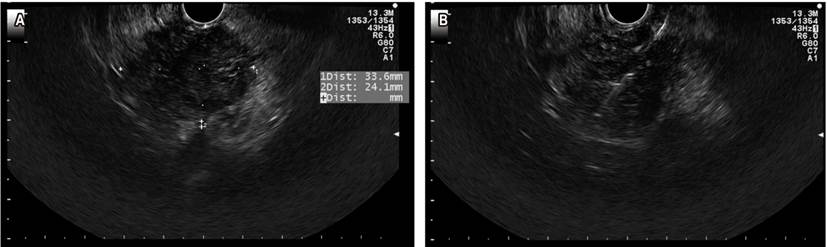

El cáncer de páncreas es altamente letal, es la cuarta causa de muerte por cáncer en Estados Unidos. El tratamiento quirúrgico mediante una duodenopancreatectomía con técnica de Whipple es una opción curativa, pero solo el 15 % de los pacientes es candidato en el momento de presentación. En estadios avanzados, la supervivencia con quimioterapia es 8,5 meses (30). El USE ha sido un método que ha venido ganando terreno en el abordaje de patologías biliopancreáticas, con una precisión diagnóstica que varía entre el 78 % y 98 %. El rendimiento diagnóstico del USE aumenta cuando se adiciona PAAF o BAAF (lesión sólida en la cabeza de páncreas en la que se realizó una PAAF, Figura 6).

La precisión diagnóstica está influenciada por factores propios de la lesión como la localización, tamaño y tipo; de aspectos técnicos como el número de pases; la técnica utilizada para el muestreo (aspiración, técnica de slow pull, técnica de Fanning); la experiencia del endoscopista; y entre los factores menos estudiados está la presencia de patólogo en sala.

El USE-PAAF es el método de elección para la toma de muestras de lesiones sólidas pancreáticas 30-32. Se considera que es más sensible que la TAC de abdomen y que la RMN en lesiones menores de 10 mm de tamaño. Además, es un método seguro y costo-efectivo ya que provee un alto rendimiento diagnóstico 33. Consideramos que una de las claves para obtener los mejores resultados en relación con las punciones por USE es obtener un material suficiente/representativo de la lesión y transferir adecuadamente al laboratorio de patología. En algunos centros de referencia mundial se ha realizado el USE-PAAF con patólogo en sala, esto ha permitido disminuir el número de pases y, en general, aumentar el rendimiento de la prueba. Recientemente, el grupo de trabajo del HPTU de Medellín mostró su experiencia preliminar de las punciones y biopsias biliopancreáticas con patólogo en sala (Figura 7). En este trabajo se resalta que dicha estrategia permitió obtener una alta eficiencia diagnóstica (cercana al 90 %), con escasos falsos negativos 34.